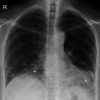

Case of Severe Treatment-Resistant Cryptogenic Organizing Pneumonia

Cryptogenic organizing pneumonia is a rare interstitial lung disease with different onset of symptoms, which responds rapidly to glucocorticoid treatment. We present a case of cryptogenic organizing pneumonia which manifested as a progressive 3-year dyspnea that ultimately has led to acute respiratory failure. Moreover, treatment with prednisone for this patient exhibited slow onset of the effect.